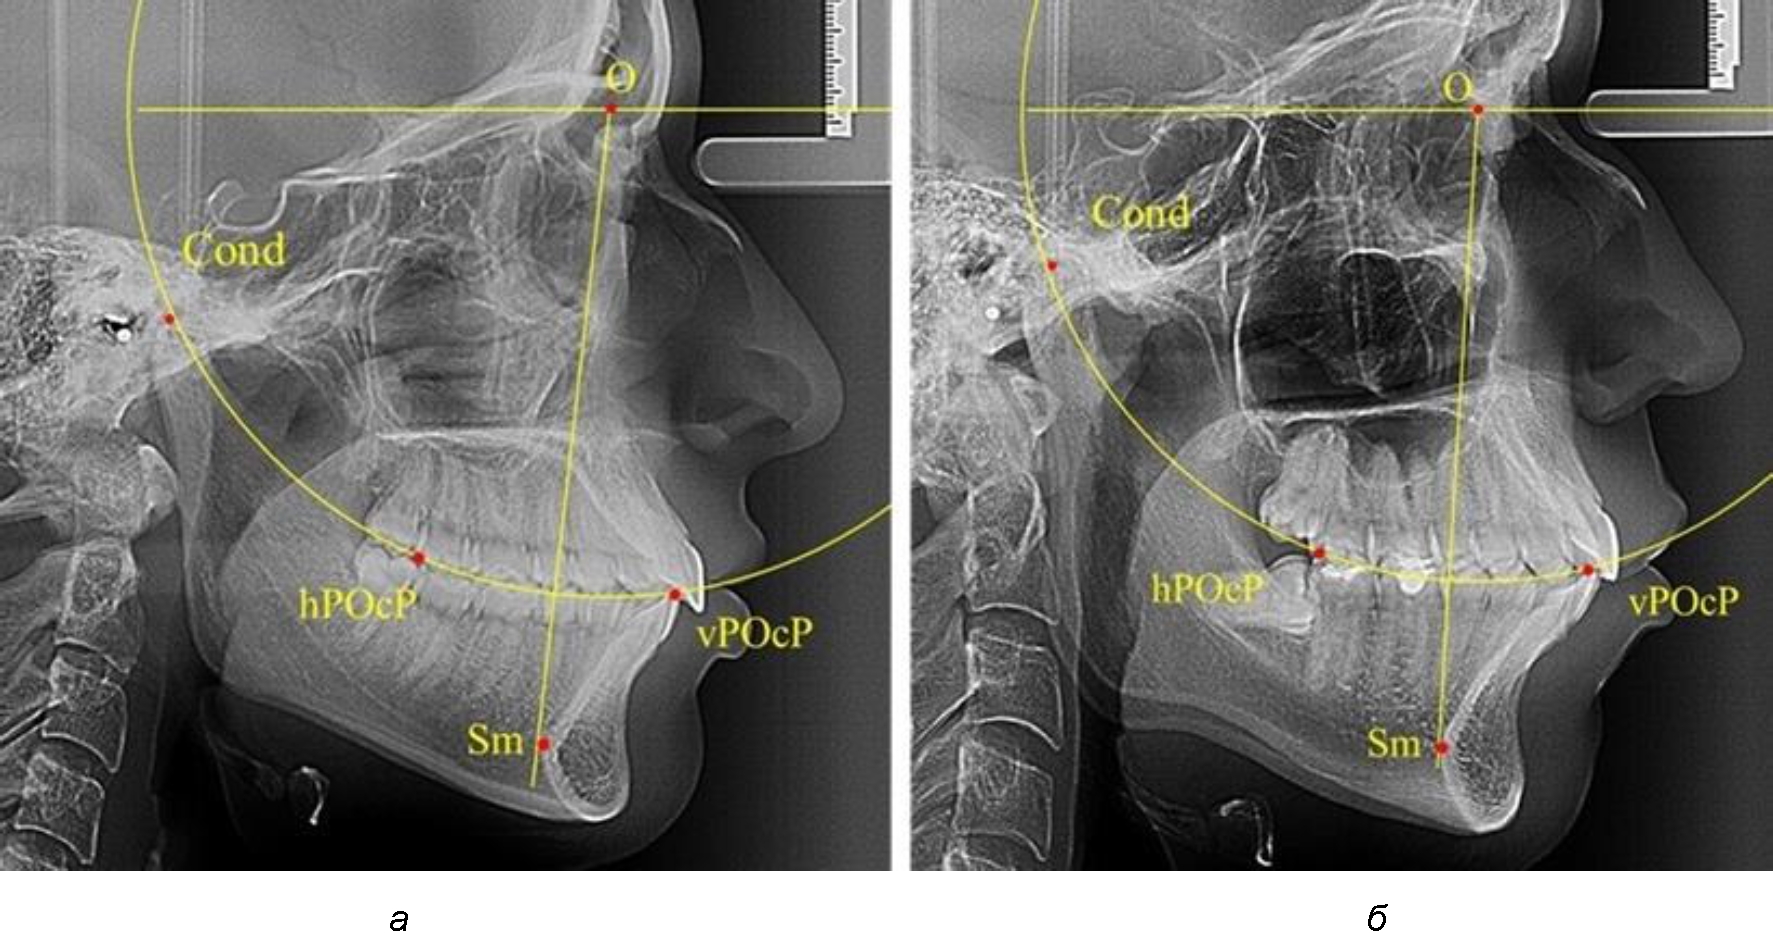

Анализ снимков проводили с использованием традиционного построения стресс-оси по Bimler. Для удобства построения использовали компьютерную программу PowerPoint. Основными точками для построения круга были передняя (vPOcP) и дистальная (hPOcP) окклюзионные точки, а также верхняя выпуклость суставной головки (Cond).

Вставка из программы в виде овала накладывалась на фотографию рентгенограммы и ручным способом растягивалась так, чтобы получился круг, проходящий через обозначенные реперные точки.

Центр окружности О, соединяющей точку резцового перекрытия с жевательной поверхностью зубов и серединой суставных головок, соединяли с выступающей точкой Sm на внутреннем контуре подбородка (рис. 1).

Рис. 1. Метод анализа ТРГ по Bimler

Результаты исследования рентгенограмм с мезотрузионным типом резцов показали, что линия Bimler проходила позади первых премоляров у людей с широким типом подбородочного выступа, однако окклюзия была физиологической и не требовала удаления премоляров, что носило рекомендательный характер при проведении подобных исследований при аномалиях прикуса. У людей со средними формами подбородочного выступа линия Bimler проходила впереди первых премоляров (рис. 2).

Аналогичная ситуация была у людей и с узкими вариантами подбородочного выступа.

Таким образом, при мезотрузионном типе зубочелюстных дуг расположение премоляра впереди линии Bimler при широких вариантах подбородка не может быть критерием выбора экстракционных методов лечения.

Рис. 2. Положение первых верхних премоляров при мезотрузии с широкими (а) и средними (б) размерами подбородка